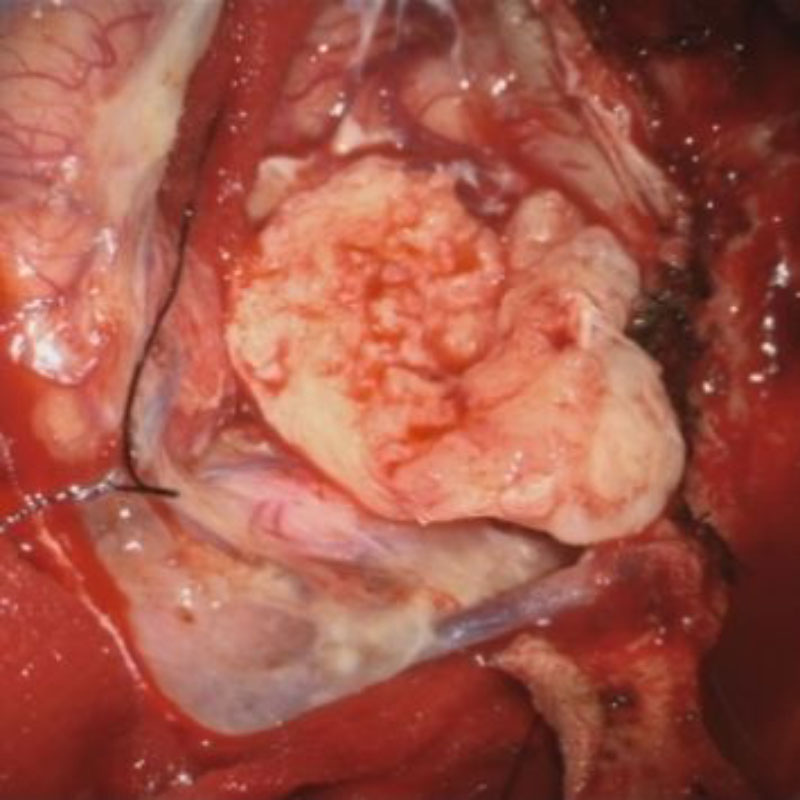

698

'25年11月

40代

右前頭葉腫瘍

頭蓋内腫瘍摘出術

No.’25_100 手術前1

No.’25_100 手術前2

No.’25_100 摘出 前

No.’25_100  摘出 中

No.’25_100 摘出 後